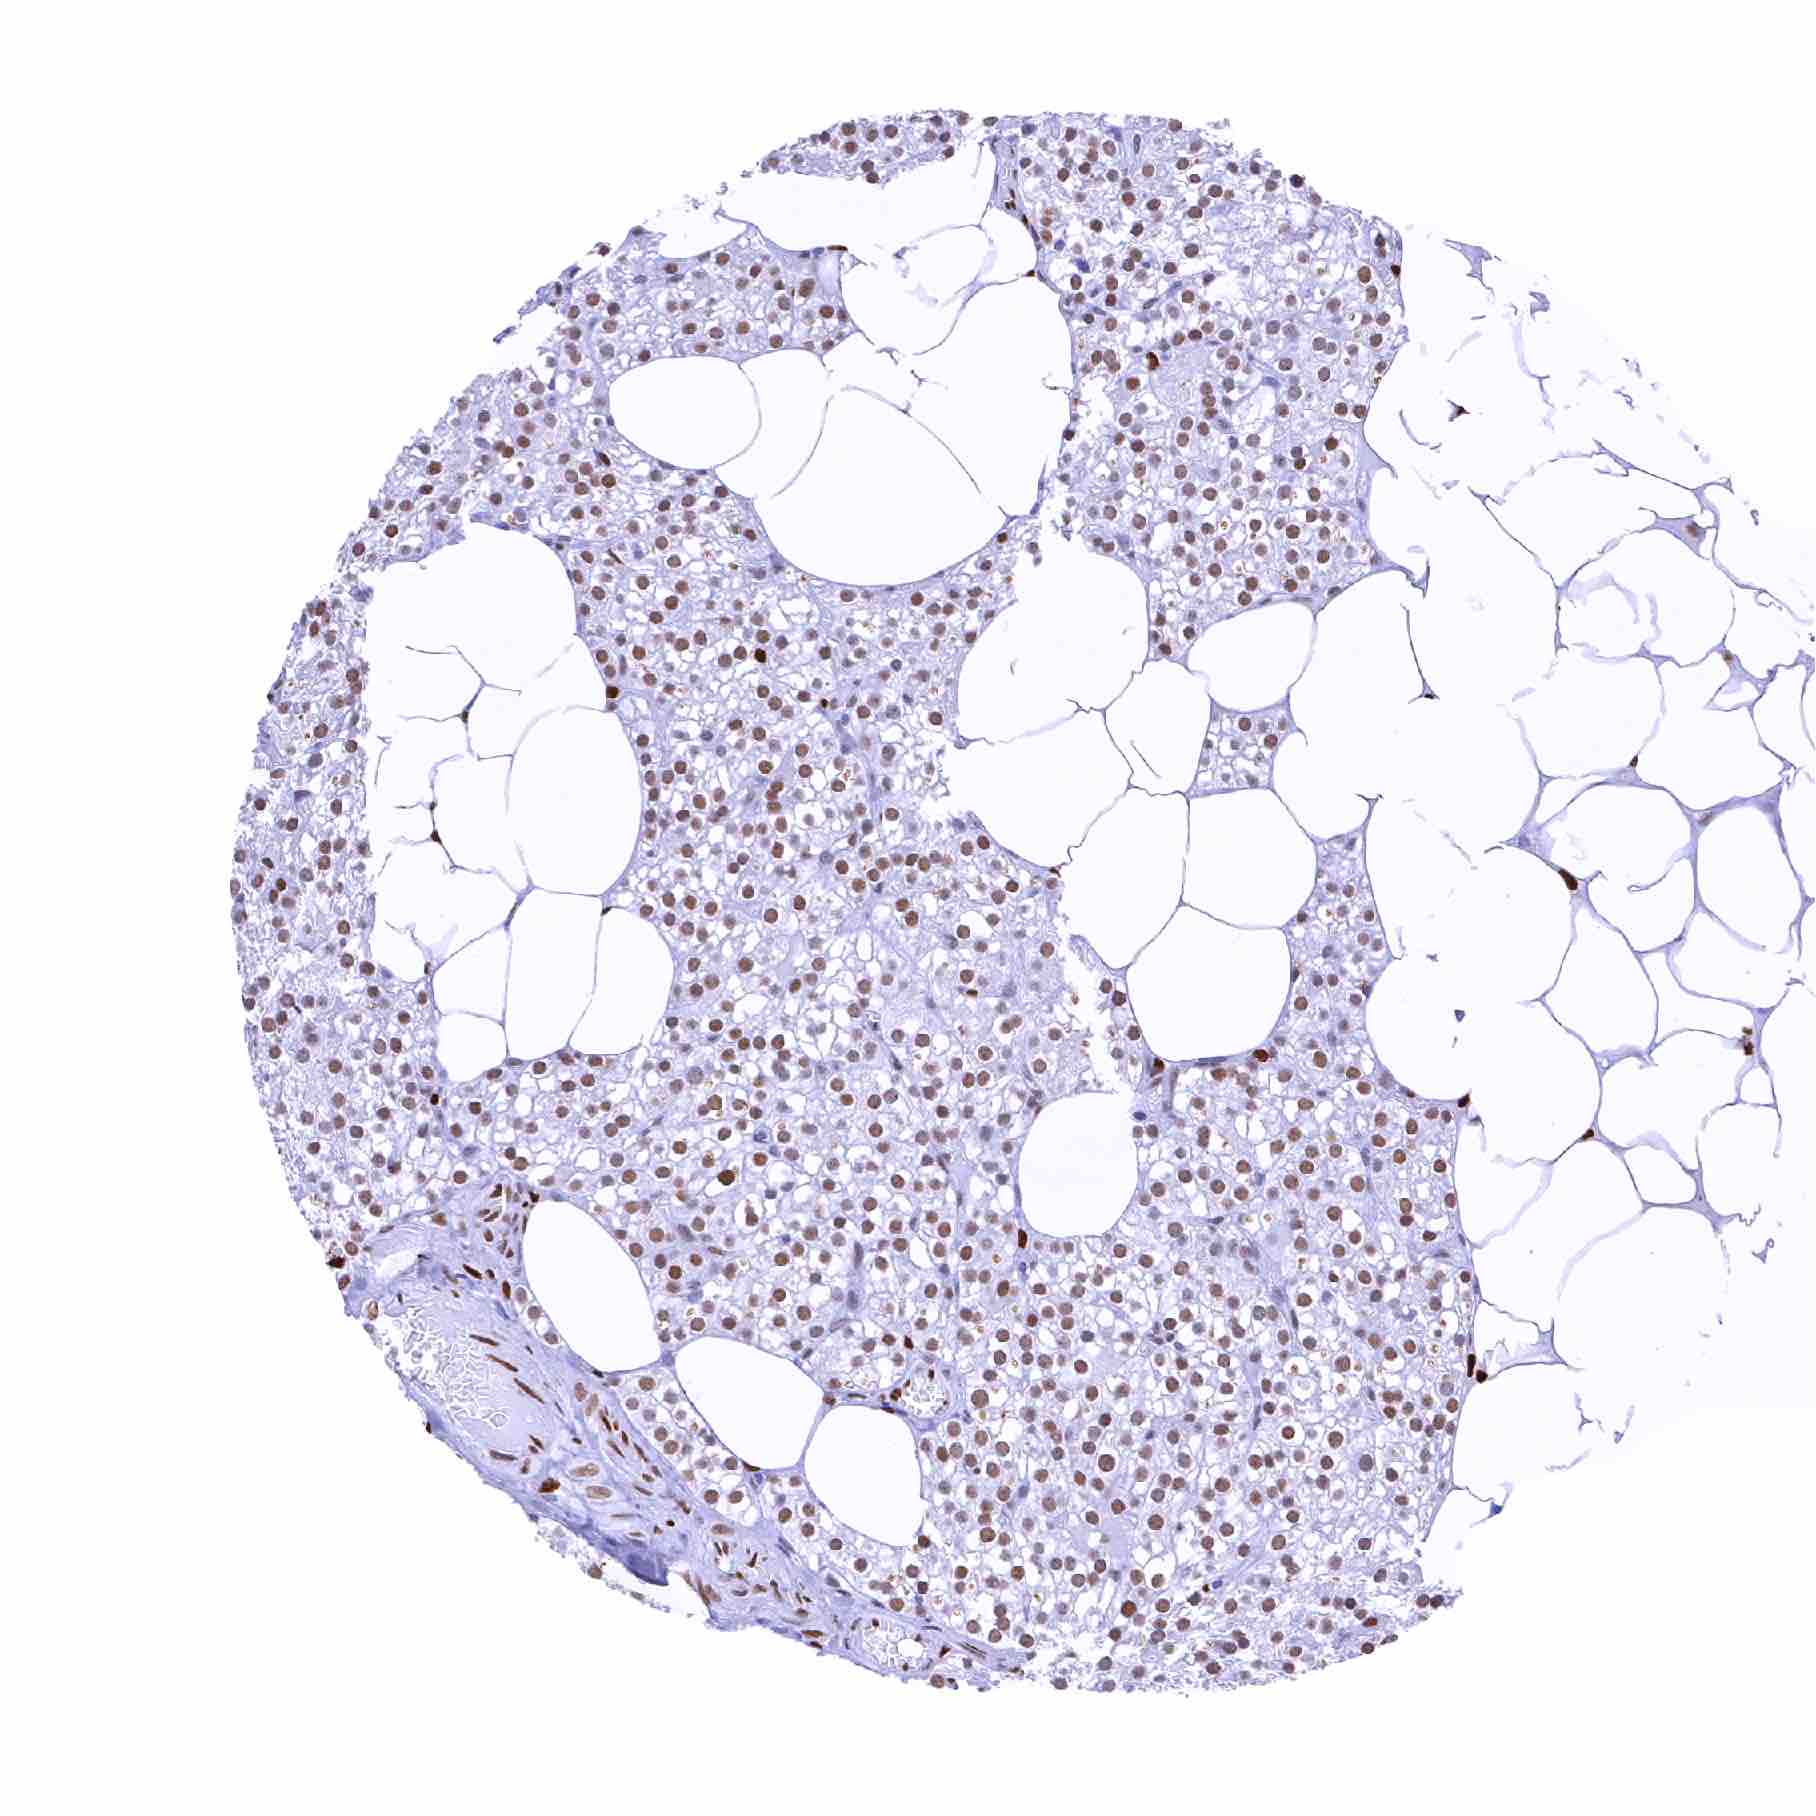

| Urinary bladder, muscular wall – Distinct nuclear staining of smooth muscle cells and of other cell types |